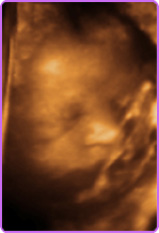

Live 3/4 D Ultraschall

35. SSW